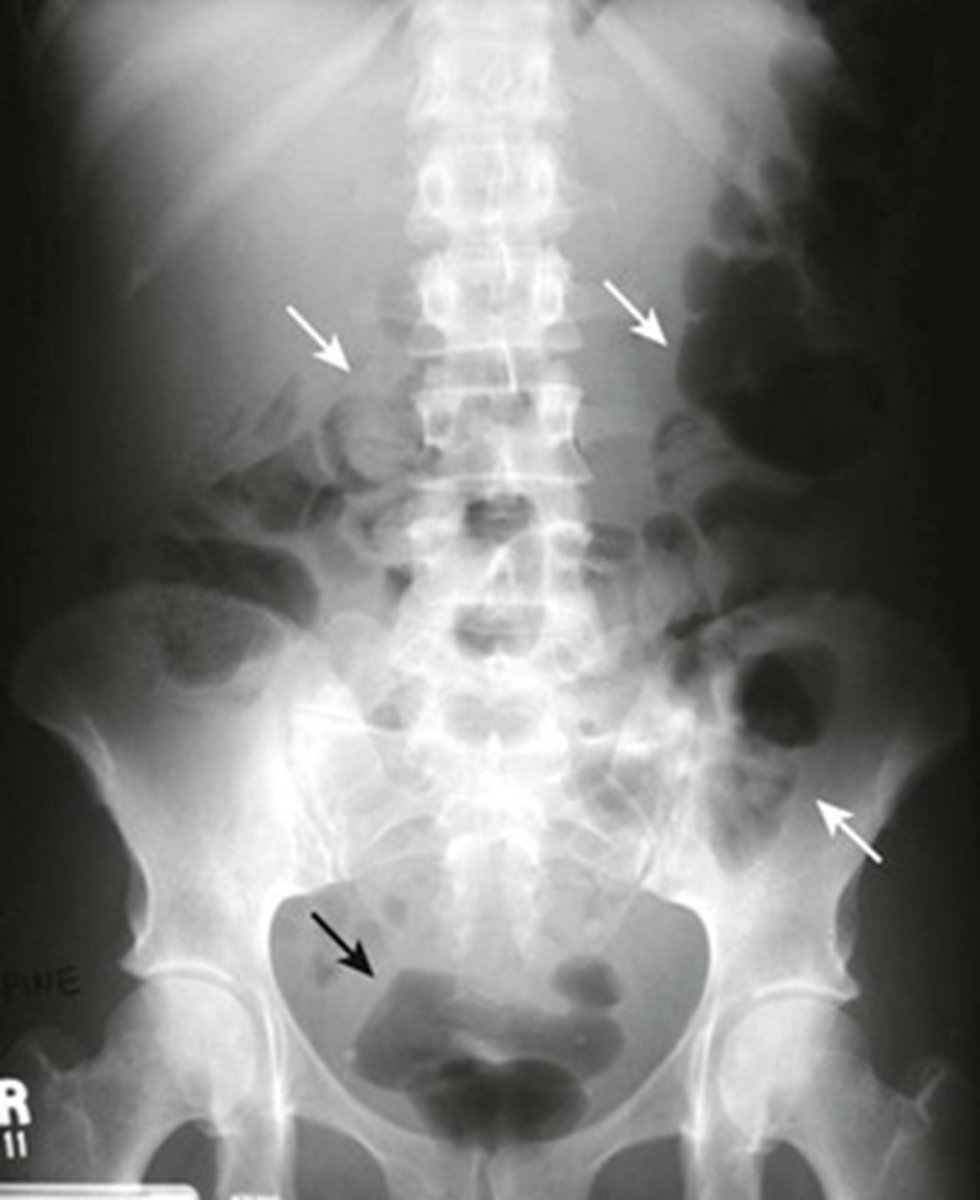

Normal prone abdomen

BLACK ARROW: S-shaped rectosigmoid colon.

WHITE ARROWS: air throughout the remainder of colon

In prone position, ascending, descending and rectosigmoid colon are the highest parts of the large bowl and will fill with air.